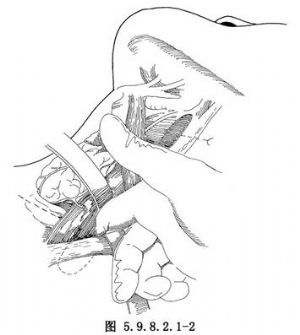

食管穿孔較爲少見,但隨着診斷技術和對本病認識的不斷提高,又由於大量開展食管內鏡檢查和食管擴張治療等,食管穿孔的發生率較過去明顯增加。引起食管穿孔的主要原因有:①損傷性食管穿孔,損傷性食管穿孔可可由槍彈傷、刀刺傷引起。胸骨與脊柱間突然受壓的閉合性胸部外傷也可能導致食管破裂,但由於食管位於後縱隔內,與心臟大血管等重要臟器相鄰,因此單獨引起胸內食管損傷者罕見,常合併心臟大血管損傷,多來不及搶救而死亡。臨牀見到的多爲頸部食管穿孔。除上述原因外,國內曾有多起輪胎爆炸,氣浪衝擊經口腔使食管發生破裂的報道。②醫源性食管穿孔,主要在食管內鏡檢查(圖5.9.8.2.1-0-1)、食管狹窄擴張、食管腔內置管、食管異物取出等診治過程中發生,多因操作不慎或食管有潛在病變而導致穿孔。其發生率佔食管穿孔的60%~70%。③異物性食管穿孔,異物性食管穿孔發生率僅次於醫源性食管穿孔。常見的原因是誤吞魚骨、雞骨、義齒等,大多爲不規整、銳利或體積較大的異物,可直接刺穿食管壁或壓迫使食管壁壞死或巨大異物使食管壁撕裂穿孔。④腐蝕性食管穿孔,吞服大量強酸或強鹼性腐蝕劑,可造成食管全層的嚴重損傷及食管穿孔。⑤自發性食管穿孔,自發性食管穿孔的原因目前尚不清楚,多與大量飲酒及暴食後發生嘔吐有關,嘔吐使腹內壓突然增高,擠壓胃部使食管腔內壓力驟然增高,同時環嚥肌反應性痙攣呈收縮狀態,致使管腔內壓力和胸腔內壓力在瞬間相差很大,引起食管破裂。偶爾也可發生於腹部用力動作時,如作嘔、分娩、癲癇抽搐、哮喘、舉重或大便等。食管穿孔後,有強烈刺激作用的胃內容物及帶有各種細菌的口腔分泌物和食物迅速經破口進入縱隔,引起嚴重的縱隔感染。由於縱隔爲疏鬆結締組織,再加上負壓及心臟大血管搏動等因素,易導致炎症在縱隔內迅速擴散,並可侵蝕穿破胸膜進入胸腔,形成一側或雙側液氣胸。縱隔及胸腔嚴重感染,胸膜腔大量滲出及毒素吸收,可很快發生休克(圖5.9.8.2.1-0-2)。吞嚥使空氣由破口進入胸膜腔,造成張力性氣胸,更加重呼吸、循環功能紊亂(圖5.9.8.2.1-0-3)。若爲腐蝕性或異物導致的食管穿孔,可引起鄰近大血管的損傷及發生大出血,如不及時救治,患者可迅速死亡。